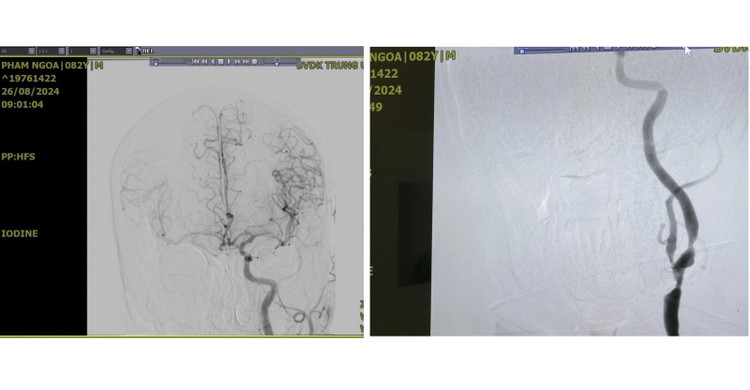

| Hình ảnh chụp DSA trước phẫu thuật của người bệnh cho thấy hai bán cầu đại não được cung cấp chỉ duy nhất 1 động mạch cảnh trái đang bị hẹp nặng - Ảnh: BVCC |